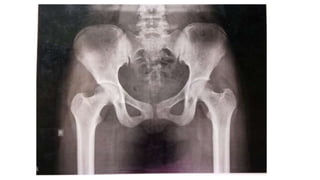

PELVIS

Triradiate cartliage

Ilia crest

Ischial tuberosity

Ischiopubic ramus

14 yr (18yr) (11-14 yr) (7-8 yr) 16 yr (19 yr-F) (21 yr -M) PELVIS Triradiate cartliage Ilia crest Ischial tuberosity Ischiopubic ramus